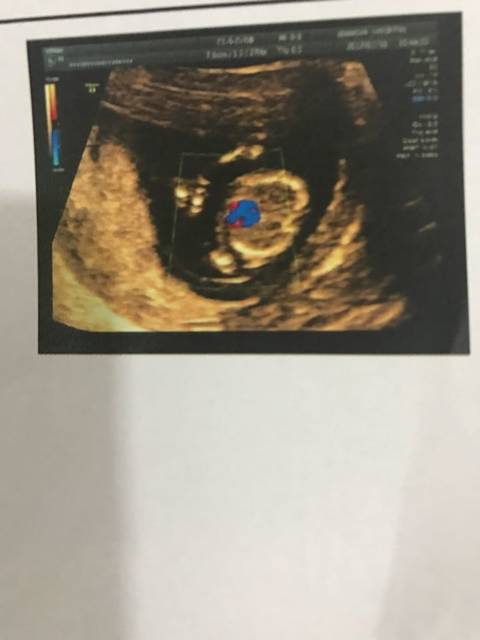

nt检查_做了nt检查,检测报告截图的彩色部分代

NT检查这是宝宝的什么部位,看不懂,有看懂的吗